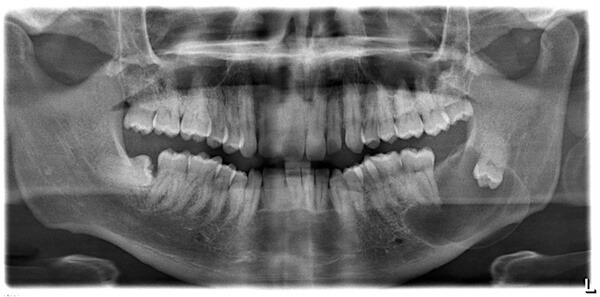

그냥 두면 문제? 사랑니 뽑아야하는 이유는?

충치 및 부정교합의 원인? 사랑니를 뽑아야 하는 이유

사랑니는 마치 첫사랑을 앓듯이 아프다고 하여 붙여진 명칭으로, 명칭 자체만 놓고 보면 아름답지만 실제로는 사랑니 때문에 고통을 받는 사람들이 많다. 사랑니는 큰 어금니 중 세 번째 위치인 제3대구치를 말하는데, 구강 내에 가장 늦게 나오는 치아다.

약 7%의 사람에게는 사랑니가 아예 없기도 하며, 입안에 가지고 있거나 나오는 개수는 1개부터 4개까지 사람마다 다르다. 사랑니가 정상적으로 나와 청결하게 유지 관리가 되면 아무 문제가 되지 않지만 대부분 치열 맨 안쪽 끝에서 공간이 부족한 상태로 자리를 잡고 있는 경우가 많아 문제가 된다. 그렇다면 정확히 어떤 문제를 야기하는지, 사랑니를 왜 뽑아야 하는 것인지 알아보자.